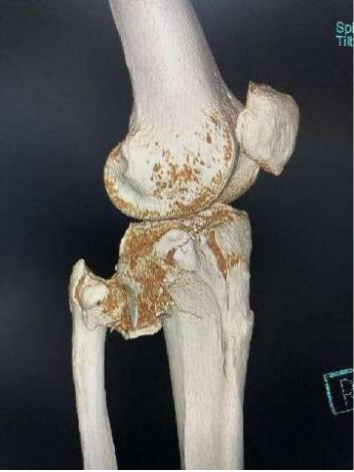

2、图3-6 术前CT见胫骨平台严重塌陷、劈裂

胫骨平台骨折的病人,如果在30年前大多数医院应该会选择保守治疗。那时CT尚未普及,而仅凭X片会低估其损伤的严重程度,容易产生可不必手术的假象,也难以准确判断骨折移位情况。即使想做手术,也没有什么好的内固定可供选用。

保守治疗肯定会遗留

膝关节功能障碍

、创伤性关节炎、跛行及畸形,造成残疾,而现在,我们采用积极的手术治疗让患者恢复了正常的外观及功能。